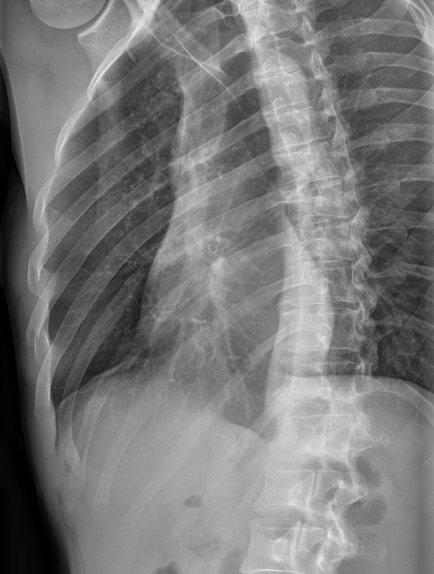

Aspect radiologique du

fracture des côtes 7th , 8th droit . Il est

difficile d'evaluer de la lesion et de la cite de

fracture sur le plain film de face PA |

|

Même cas en position OAD , on peut

detecter la fracture du co6te 7, 8th droit . |